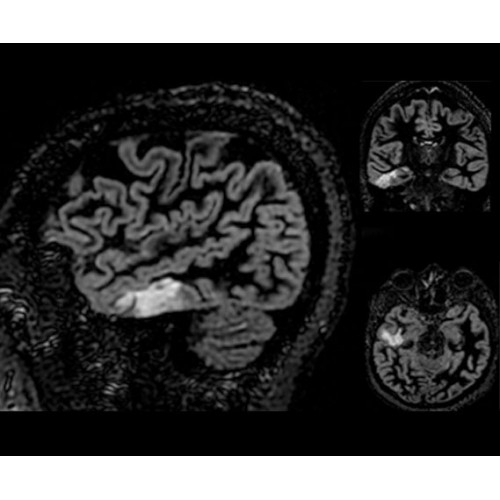

• ImageWorks — повысит производительность МРТ благодаря визуализации высокого качества с MAGIC, четкими результатами пост-процессинга с READYView.